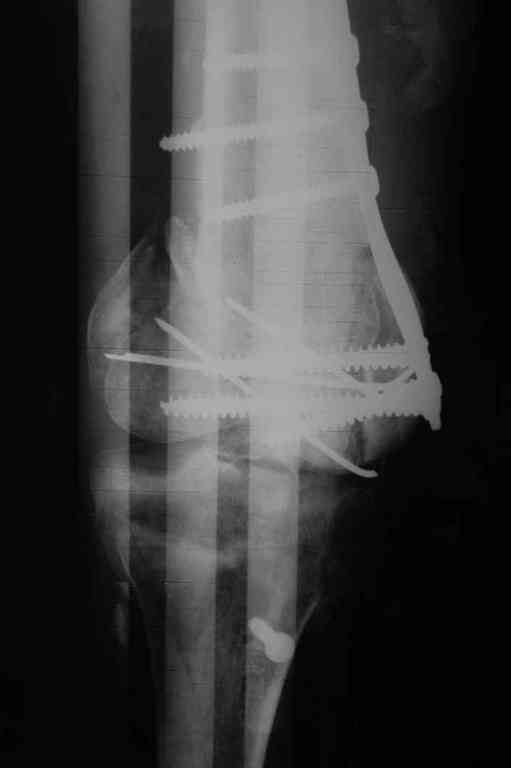

[Ortho] Последствия открытого перелома дистального отдела бедра

Имя     : 1.JPG

Тип     : image/jpeg

Размер  : 72520 байтов

Url     : http://weborto.net:8080/pipermail/ortho/attachments/20100908/be90ac55/attachment-0002.jpeg